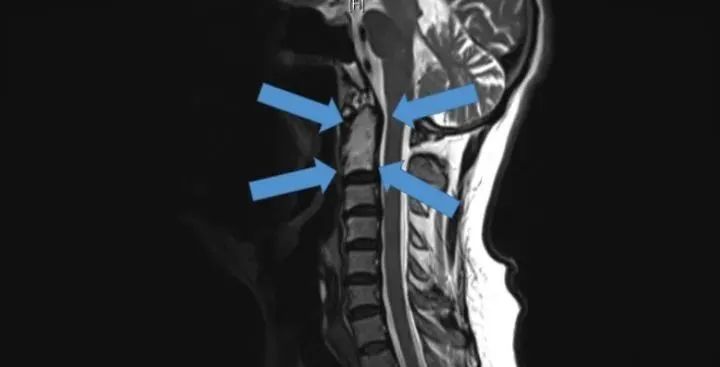

△2015年底,世界首例采用3D打印椎骨植入物

脊柱行業(yè)也是未來醫(yī)療器械市場,最新發(fā)展趨勢之一。通過3D打印技術,來達到創(chuàng)新產(chǎn)品的目的,該技術可以促進骨骼向內(nèi)生長,并改善植入物對脊柱骨的固定,縮短制造流程,提高患者滿意度,從而在某些情況下更具成本效益。

例如,Medtronic鈦金屬3D打印平臺——TiONIC技術。使用激光方法制造具有增強表面紋理的植入物。Artic-L是該公司使用TiONIC技術制造的第一款金屬植入物。可供外科醫(yī)生在脊柱手術中使用。還有K2M的Lamellar,同樣采用鈦制造3D脊柱植入物。使用金屬3D打印技術特有的優(yōu)勢之一,可實現(xiàn)曾經(jīng)被傳統(tǒng)制造技術,認為不切實際的結構。